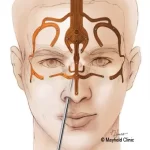

۱. جراحی

به دلیل حساسیت زیاد عصب بینایی، جراحی فقط در موارد زیر توصیه میشود:

- تومور باعث فشار شدید روی مسیر بینایی شده باشد

- یک چشم در حال از دست رفتن کامل بینایی باشد

- تومور در نواحی قابل جراحی قرار داشته باشد

دکتر حسن محمدی با بهرهگیری از تکنیکهای دقیق جراحی مغز و اعصاب، خطر آسیب به بافتهای حساس را به حداقل میرساند.